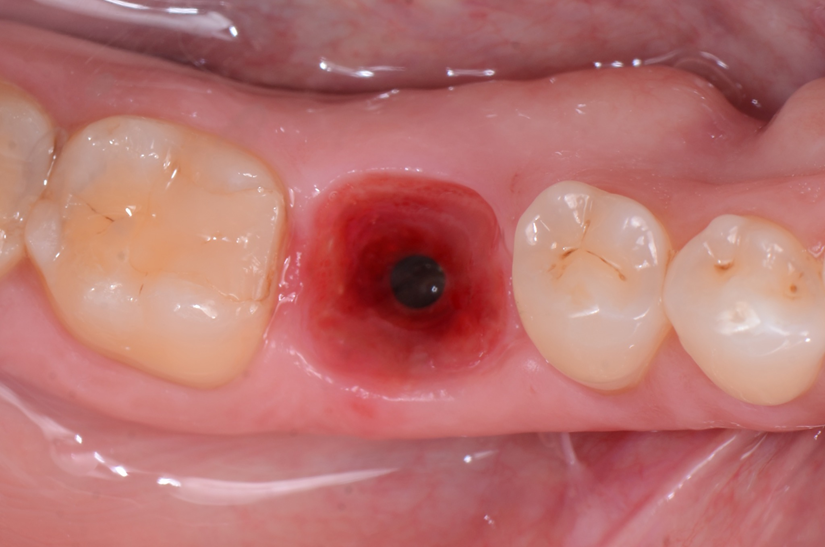

O paciente apresentou fratura vertical mésio-distal no elemento 46. Foi planejada a exodontia minimamente traumática e instalação imediata do implante Maestro Superiore (Implacil Osstem) utilizando uma guia prototipada. Após a exodontia, o implante foi instalado seguindo o protocolo de cirurgia guiada. O GAP vestibular foi preenchido com o Extra Graft. Um cicatrizador personalizado impresso com haletas facilitadoras foi capturado com resina flow e instalado. Após 30 dias, foi realizado escaneamento indireto para obtenção do perfil de emergência, utilizando protocolo digital com sobreposição do cicatrizador escaneado para confecção da coroa definitiva em zircônia policristalina estabilizada por ítria.